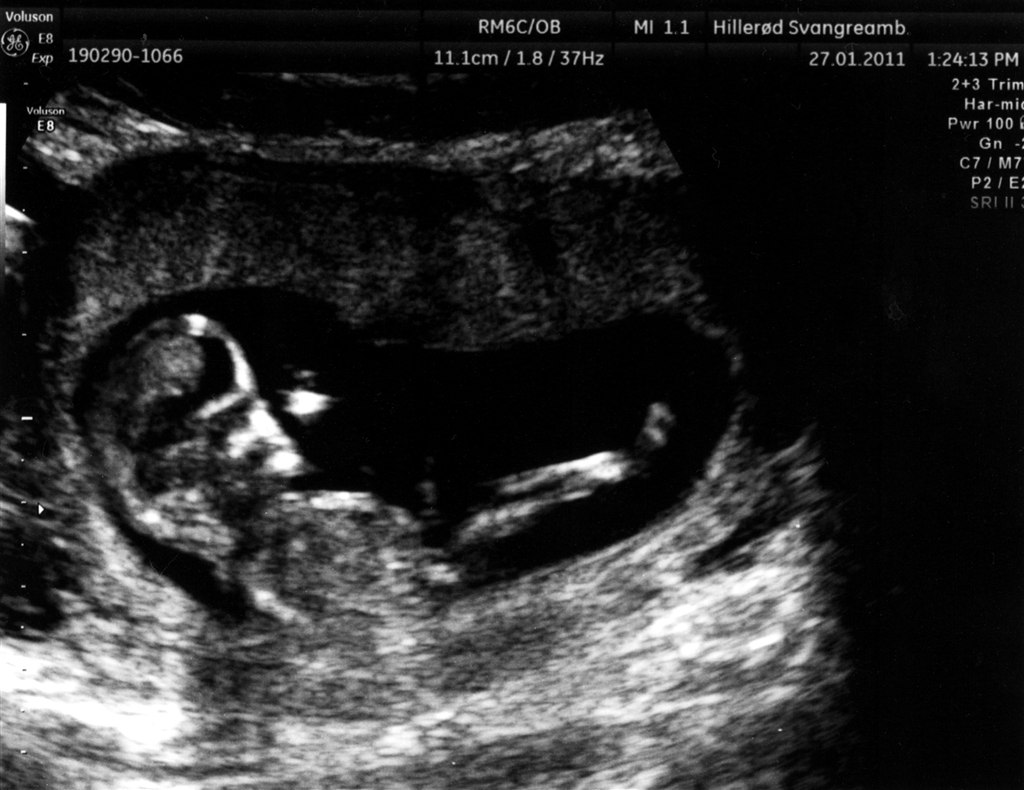

.. Så fik mig og min søde kæreste endelig set det lille liv!

Så fantastisk - intet mindre !

Alt var som det skulle være, og vi har et sundt og rask lille ven, liggende i sin lille hule.

Vedhæftede fotos (klik for at se i fuld størrelse)